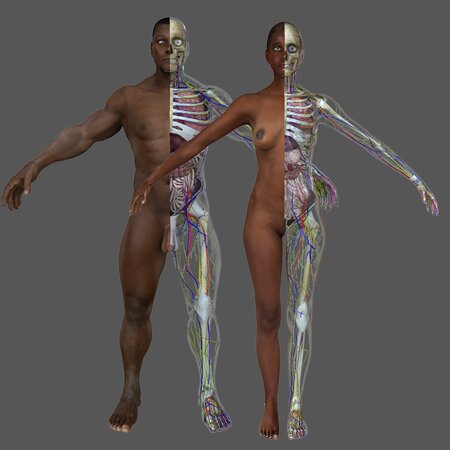

An aesthetic, accurate and easy to understand depiction of the very complex Human Urinary & Cardiovascular System

Heart is animated using morph targets set up appropriately in the respective 3D applications.

A transparent human model is included to give a sense of the organ's location, without cluttering the important details inside.

Optimized subdivision cage gives smooth edges even in high definition. Just step up the subdivision levels.

Heart is textured and bump mapped with 2048 x 2048 image. Materials are applied to all objects.

Arteries and Veins correctly marked in Red and Blue respectively.

Depicted Organs:

Urinary System: Kidney, Urethra, Bladder, Suprarenal Gland.

Cardiovascular / Circulatory System: Heart, Veins and Arteries to various parts of the body.